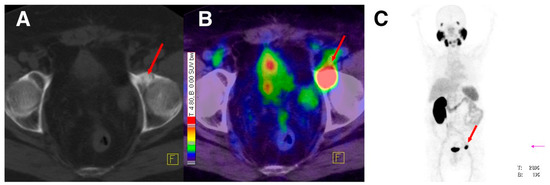

177Lu-labeled monoclonal antibody J591, which binds to the extracellular domain of PSMA, was firstly used for radionuclide therapy of prostate cancer [149]. Although the response to therapy was encouraging, the dose-limiting toxicity which is transient myelosuppression was the major reason of abandoning this therapeutic approach. In contrast, the development and preclinical evaluation of new PSMA ligands which could be labeled with therapeutic radionuclides such as 177Lu, paved the way for the reinvestigation of the 177Lu-based radionuclide therapy in patients with advanced prostate cancer. The radiotracers which have been used of the conduction of those studies are 177Lu-PSMA-617 and 177Lu-PSMA I&T (Figure 21). The clinical trials reported so far demonstrate promising results [150,151,152,153,154,155,156] with a mean tumor dose 6 to 12 fold higher compared to other critical organs such as kidneys and salivary glands. The PSA levels were found to be reduced in 60–90% of the patients after a single dose of both 177Lu-labeled PSMA-based radiotracers. The patients tolerated the therapy well, with no significant nephrotoxicity and just rarely occurring other severe side effects were observed. Although PSMA-directed radionuclide therapy bears a potential for implementation in routine clinical practice, the limited number of studies so far requires further controlled clinical trials for the establishment of the clinical value of 177Lu-PSMA-617 and 177Lu-PSMA I&T. 177Lu-PSMA-617 recently received FDA approval for phase II clinical trials in the U.S., (“First U.S. multi-center investigational clinical trial of 177Lu-PSMA-617 targeted radioligand therapy in metastatic castration resistant prostate cancer receives FDA clearance”. Daily Tribune, SyndiGate Media Inc. (Houston, TX, USA); 7 February, 2017, as found on http://www.pharmacychoice.com/News/article.cfm?Article_ID= 1690538).

Figure 21.

70-year-old patient with PSMA-avid lymph node metastases on 68Ga-PSMA PET/CT before therapy (A) and on 177Lu-PSMA I&T scintigraphy after first PSMA radionuclide therapy (B); with remarkable reduction in uptake after second PSMA RLT (C). Results were consistent with excellent therapy response projection (Reprinted with permission of [153]).